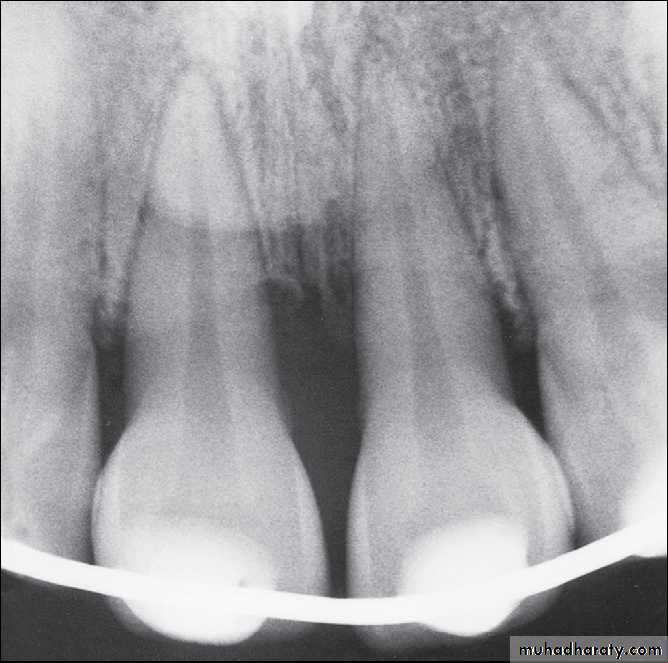

Radiographs of extruded tooth before and after repositioning and stabilization with acid-etch composite technique.